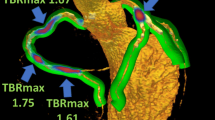

Compared with patients with lower coronary microcalcification activity (< 1.42, n = 50), the aortic microcalcification activity was significantly increased (1.44 [1.29-1.65] vs 1.16 [1.06-1.28]; P < .001) in patients with higher coronary microcalcification activity (≥ 1.42, n = 50) (Figure 2A). The aortic microcalcification activity was also significantly correlated with the coronary microcalcification activity (r = 0.70, P < .001) (Figure 2B). Moreover, after adjustment confounding factors (age, gender, body-mass index), increased coronary microcalcification activity was independently associated with the aortic microcalcification activity (Beta: 0.445 per SD increase; 95% confidence interval: 0.303 to 0.587; P < 0.001) by multiple linear regression analysis. After adjustment for SYNTAX score and coronary artery calcium score, higher coronary microcalcification activity was also independently associated with the aortic microcalcification activity (Beta: 0.515 per SD increase; 95% confidence interval: 0.311 to 0.719; P < .001). Concordant associations were found after adjustment for combined cardiac risk factors and serum biomarkers (Table 2). Representative images in patients with significantly elevated coronary 18F-NaF uptake and aortic 18F-NaF uptake are illustrated in Figure 3.

Correlation between the CMA and the AMA. Patient with higher CMA (≥ 1.42) had a higher AMA [1.44 (1.29-1.65) vs 1.16 (1.06-1.28); P < .001) than those with lower CMA (< 1.42) (A). There was a moderate correlation between the CMA and the AMA (r = 0.70; P < .001) (B). CMA, coronary microcalcification activity; AMA, aortic microcalcification activity

Representative case showing the 18F-NaF PET/CT in patients with significantly elevated coronary and aortic 18F-NaF uptake. Patient (male; 72 years) suffered multivessel lesions presenting an intense focal 18F-NaF uptake in LCX and RCA (A-C). Coronal view of the thorax showing increased 18F-NaF uptake in the ascending aorta (D-F) and aortic arch (G-I). Short-axis view of the thorax showing increased 18F-NaF uptake in the aortic arch (J-L). 18F-NaF, 18F-sodium fluoride; LCX, left circumflex; PET/CT, positron emission tomography/computed tomography; RCA, right coronary artery